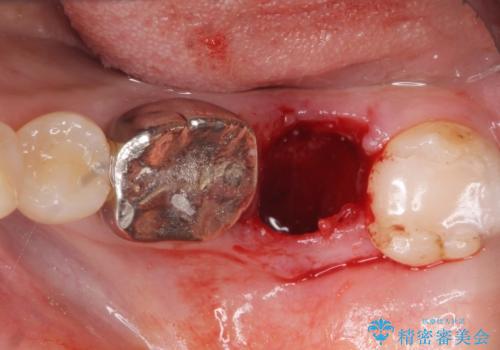

左下の奥歯(左下7)は破折しており保存不可能な状態でした。

ご希望により、隣の親知らず(左下8)を移植しました。

移植後、生着を待って根管治療及び補綴修復を行いました。